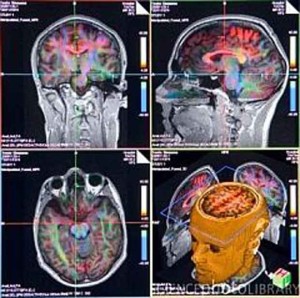

Cervello: nessuna differenza tra il maschile e il femminile

Dimenticate la teoria secondo la quale gli uomini vengono da Marte e le donne da Venere. I cervelli di Lui e Lei sono gli stessi.